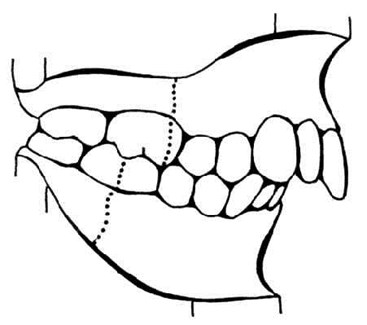

Illustration #2 of 3: End-to-End Class II Molar Relationship

This example demonstrates an end-to-end molar relationship which satisfies ABO criteria for Initial Certification only. It is to be distinguished from the full-step Class II of the preceding illustration.